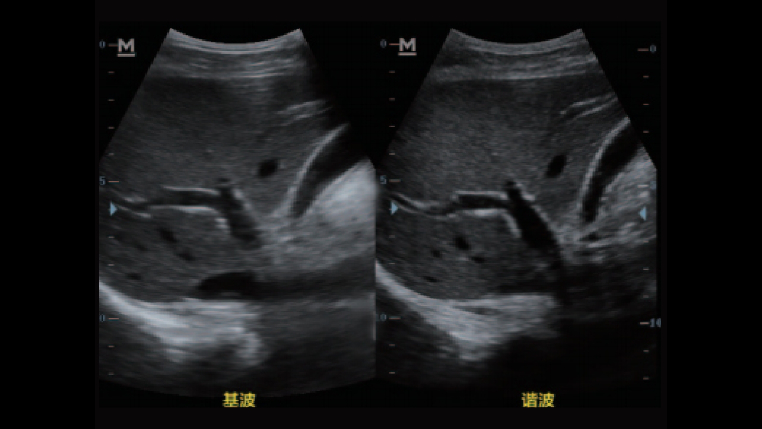

宽带频移谐波技术

可在频域上有效的分离基波和谐波,得到更纯净的谐波信号,使谐波图像质量更优